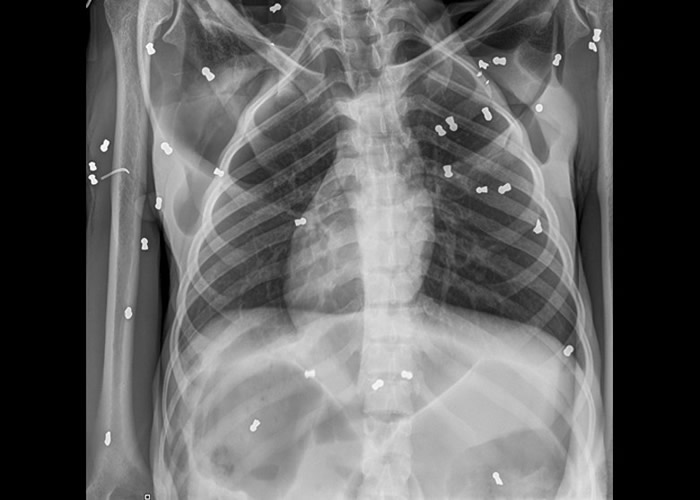

亚齐省当局于上周日(10日)接报,一只年约30岁的红毛猩猩妈妈奄奄一息地倒于树下,其身旁伴有一只年幼红毛猩猩。官员随即前往救援,惟小猩猩返魂乏术;不过猩猩妈妈则大难不死。X光片可见,猩猩体内布满子弹,触目惊心。

猩猩体内有多发子弹。